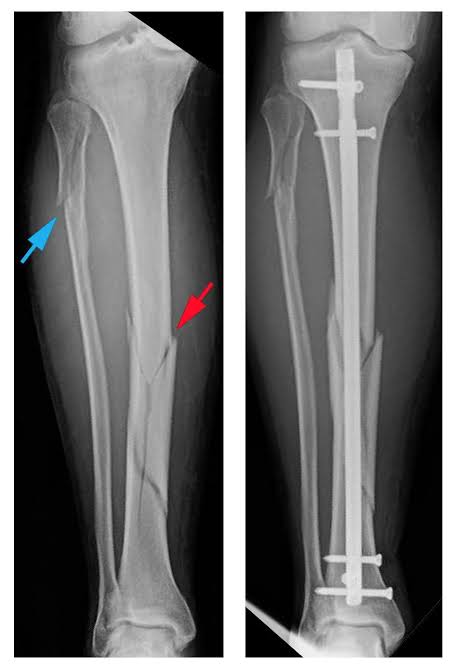

Pada kasus patah tulang,kadang dilakukan operasi utk memfiksasi tulang tujuannya agar posisinya bagus,sembuhnya bagus, bisa aktivitas lagi sprt sedia kala

Abis tulang yg patah dikembalikan ke tempatnya, kan harus dipegang dgn implant biar ga lepas lagi, biar terfiksasi bagus sampai tulangnya menyatu dan nantinya akan dilepas, implant nya klo dimasyarakat sering di sebutnya pen(plate and screw). Pen ini bisa dipasang diluar : Image

Selain pen yg dipasang di luar/permukaan tulang, pen bisa jg dipasang di dalam tulang(intramedullary nail/rod) ,antara yg di luar atau di dalam punya keunggulan masing2,sesuai kasus atau jenis patah tulangnya .. ImageImage